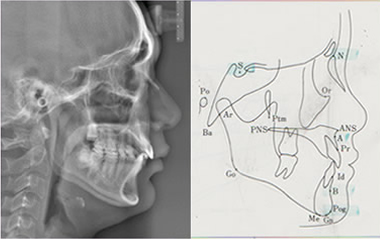

頭部Ⅹ線規格写真(セファログラム)

矯正治療前の診断時、矯正治療中の状態確認、矯正治療終了後の確認など、同じ規格で撮影したレントゲン写真があれば変化が把握できるため矯正治療で一番重要な機器としては、このセファログラムがあげられます。